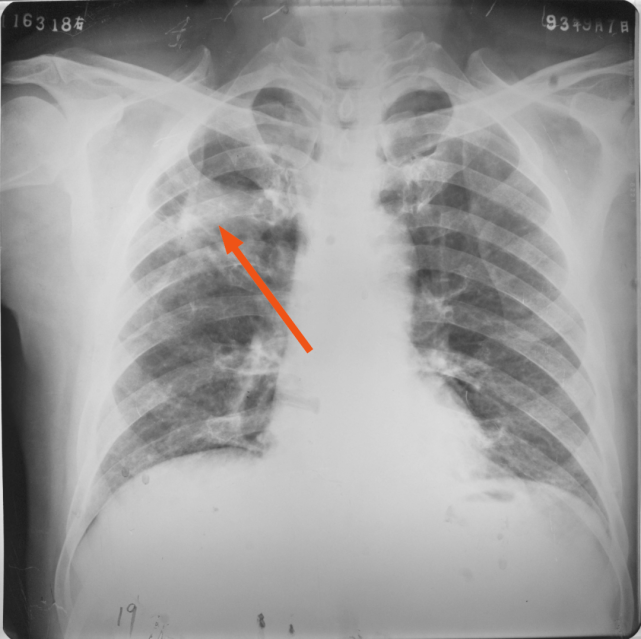

右上、下肺支原体肺炎

图片

胸部正位片示:右上、下肺野肺纹理增粗,可见斑片状阴影,密度较淡,局部呈扇形自肺门部发出(箭头所指)